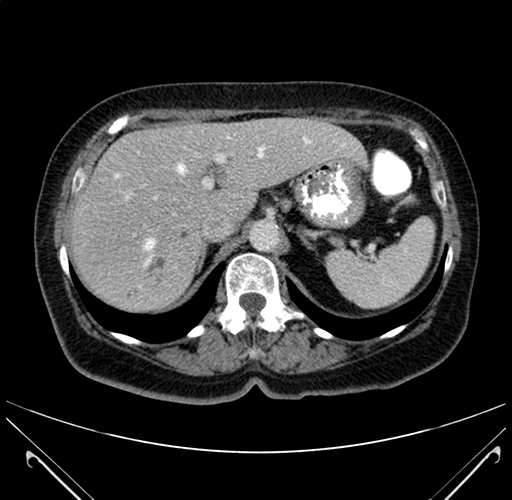

Pre-Chemo: Axial Venous